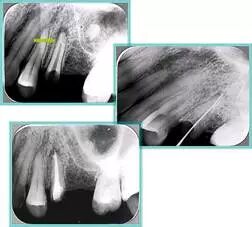

6. 钙化

常见有修复性钙化和增龄性钙化。下面为根管钙化 X 线片。

牙胶尖什么颜色​牙齿“晓”“技”|最全根管治疗的标准步骤,以及细节把握_https://www.jmylbn.com_新闻资讯_第26张

解决方法:( 1 )清楚根管系统解剖形态。( 2 )安全头的金刚砂钻开髓,低速球钻磨除钙化牙本( ET20 ,ET40 ,DG-16 )。( 3 )彻底去除髓腔周壁的牙本质龄。( 4 )借助化学性药剂,如EDTA 等。

( 5 )初锉选用 8# 或 10#K 锉,平衡力法探察到工作长度 , H锉上下提拉法使根管扩大,提高工作效率

7. 器械折断

右图及下图为器械折断的 X 线片。箭头处示折断器械。

牙胶尖什么颜色​牙齿“晓”“技”|最全根管治疗的标准步骤,以及细节把握_https://www.jmylbn.com_新闻资讯_第27张 牙胶尖什么颜色​牙齿“晓”“技”|最全根管治疗的标准步骤,以及细节把握_https://www.jmylbn.com_新闻资讯_第28张

解决方法:( 1 )取出。( 2 )通过。( 3 )重新确定工作长度,充填。( 4 )根尖手术。

器械折断可以不用取出,取出的原因多是患者心理因素。留在里面的器械关键是进行消毒,预防性使用抗感染药物,预防感染。